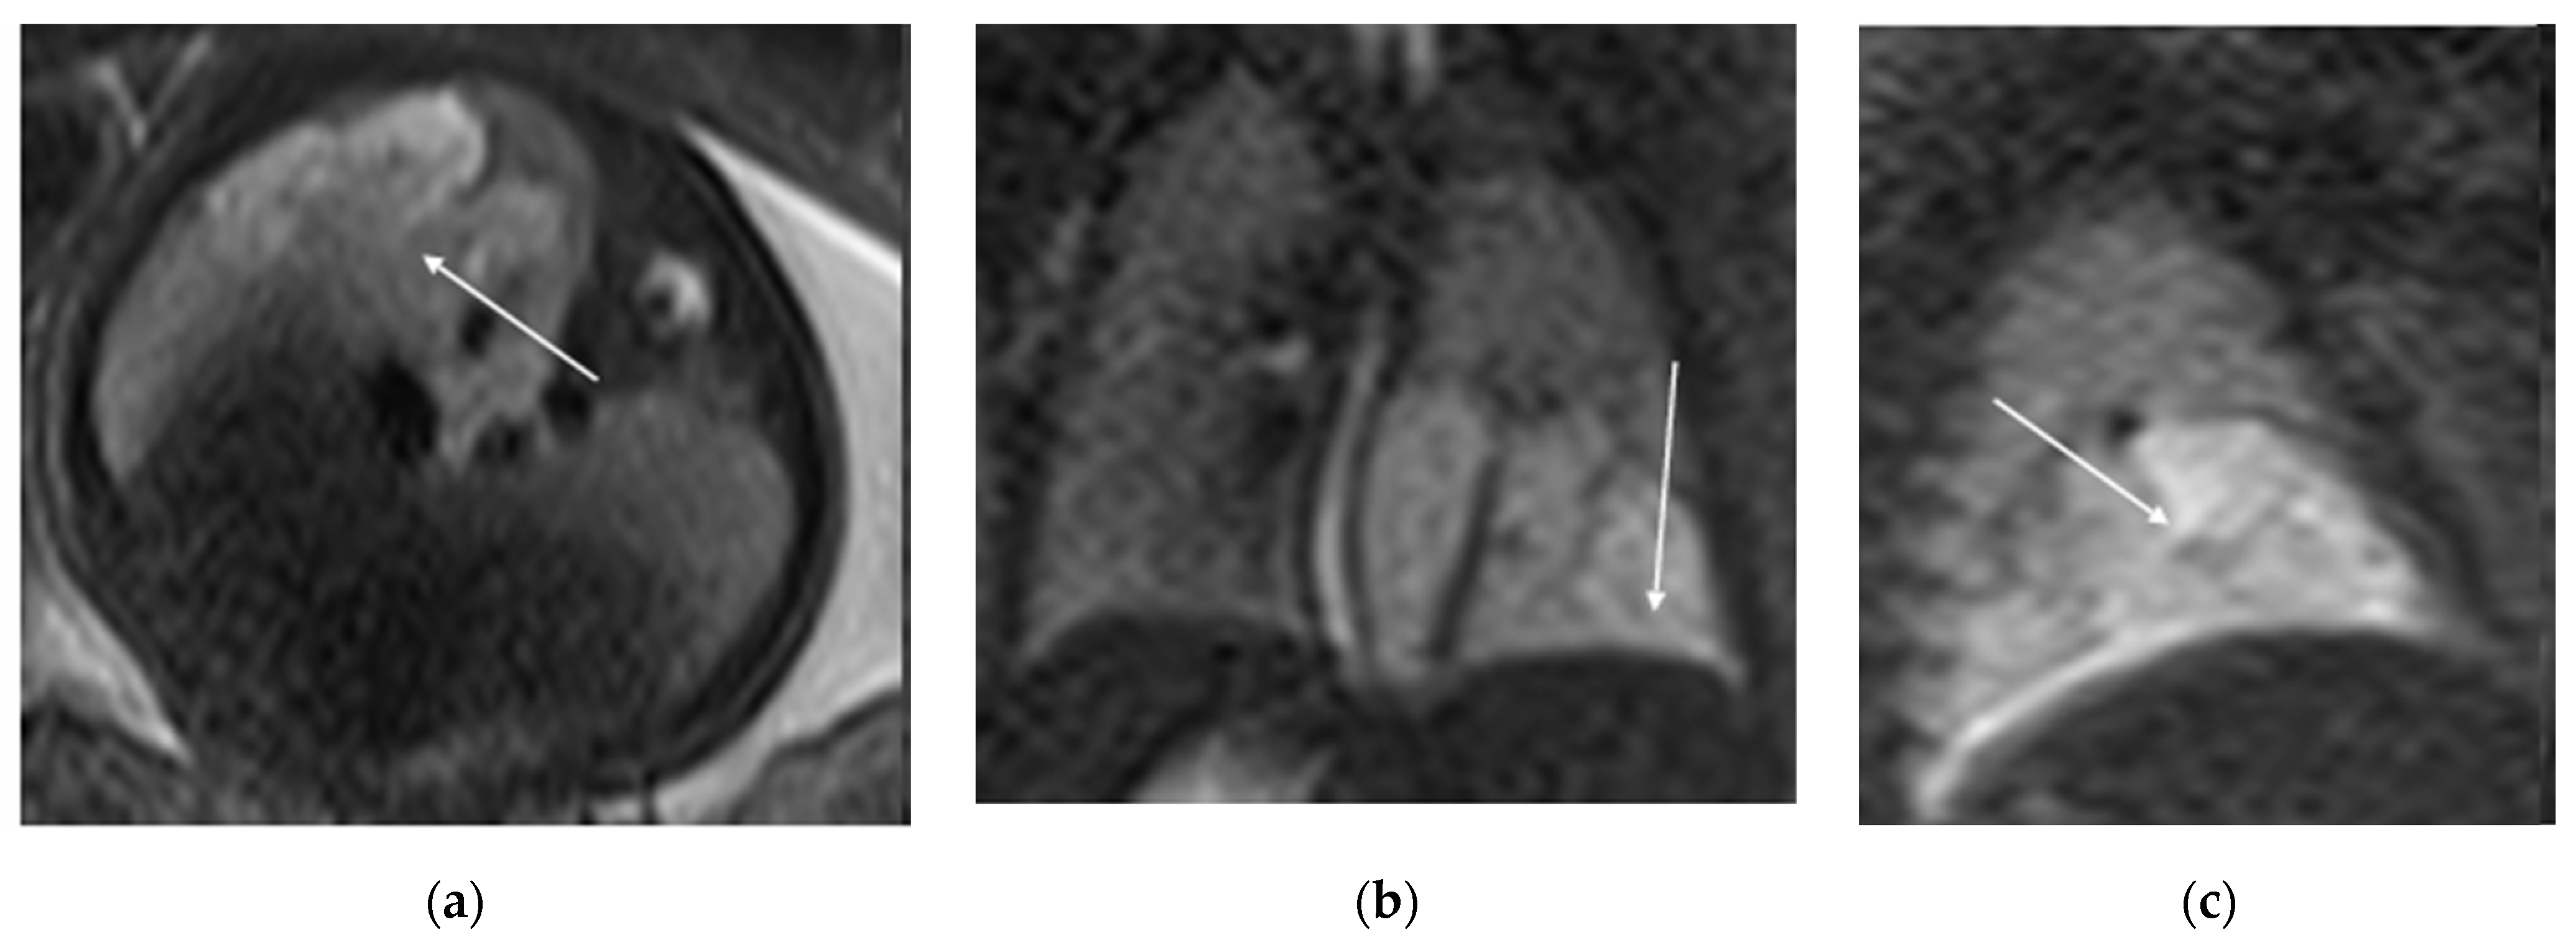

Figure 5. T2 HASTE axial plane (a), coronal (b) and sagittal (c): shows a multicystic brilliant formation (white arrow), at the level of the right and middle lower lobes. The lesion represents 55% of the right lung volume.

MRI is an alternative cross-sectional imaging modality, particularly with newer, faster sequences that improve detection of CLMs within aerated lungs, such as steady-state acquisition and single-shot fast spin echo (Figure 5). MRI can often be performed without sedation for infants under six months of age and older children who can follow breathing instructions. For children between these age groups, sedation may be necessary due to the length of the study. Chest MRI typically covers the lower neck to mid-abdomen, and acquisitions are performed in three planes, often with intravenous contrast. MR imaging also helps in surgical planning by accurately detecting soft tissue and fluid components within larger CLMs. Notably, all parenchymal CLMs demonstrate reduced enhancement at peak pulmonary perfusion after IV contrast administration.